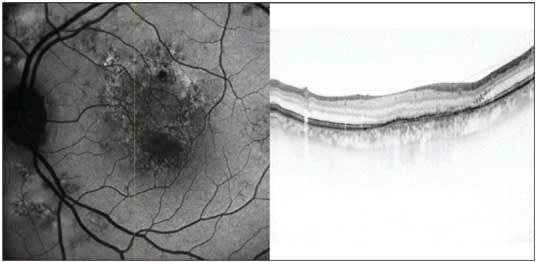

Figure 2. This figure shows an autofluorescence reflectance image with CNV and choroidal hemangioma.

"Three-D volume scans are helpful for identifying pathology in suspicious areas," he continues. "Volume scans are a series or stack of parallel B-scans, which are aligned to one of the instrument's reference fundus images, such as infrared or autofluorescence. If a suspicious area is seen, I can literally page through the B-scans to look for any signs of pathology. (Figures 1 and 2)

"Not having had previous experience with laser angiography, I was surprised with the excellent quality of fluorescein images," adds Dr. Heier. "The combination of autofluorescence, fluorescein angiography and spectral-domain OCT volume scans in one instrument lessens the likelihood of missing pathology."